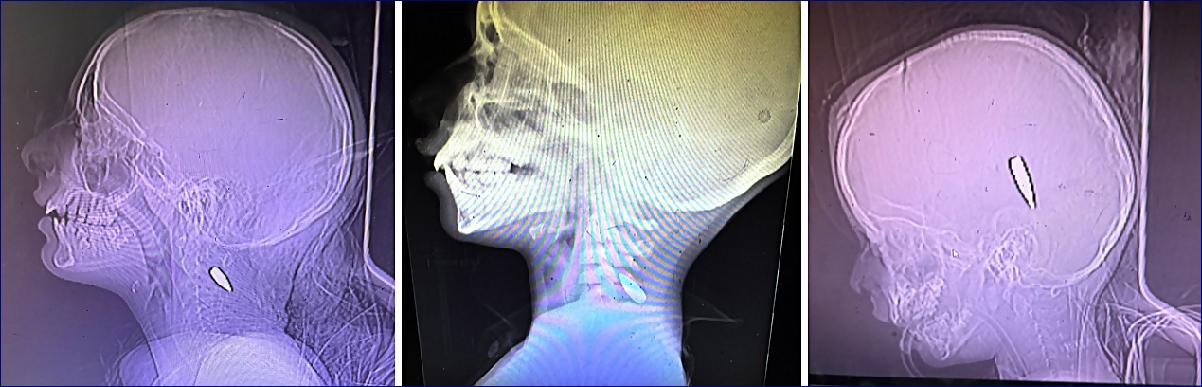

Fotografie rentgenového snímku gazanského dítěte s kulkou v krku. Fotografie rentgenového snímku gazanského dítěte s kulkou v krku. Fotografie rentgenového snímku gazanského dítěte s kulkou v hlavě.